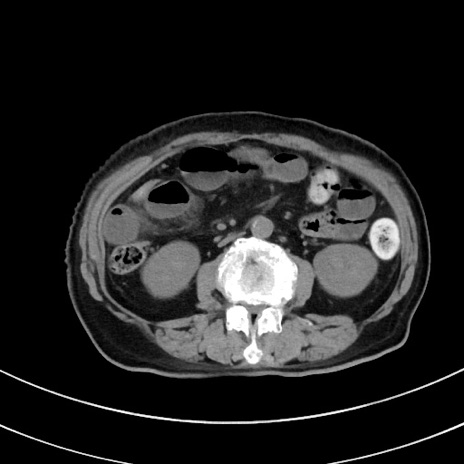

冠状断像

【症例】70歳代 女性

【主訴】心窩部痛

【現病歴】延髄病変の精査・加療にて神経内科入院中。本日より心窩部痛あり。

【既往歴】虫垂炎

【身体所見】右下腹部を中心に圧痛と反跳痛あり。

【データ】WBC 10900、CRP 0.02